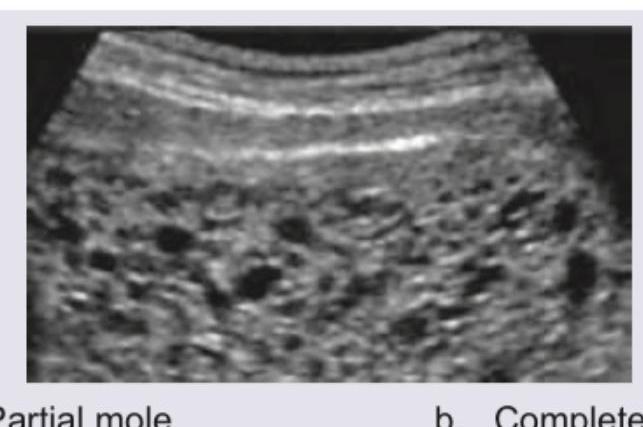

A 25-year-old presents with amenorrhea of 8 weeks. What does the USG show?

Explanation: ***Partial mole*** - The ultrasound image shows a **thickened placenta** with **multiple cystic spaces** (vesicles), often described as a "grape-like cluster" or "Swiss cheese" appearance, which is characteristic of a partial hydatidiform mole. - In a partial mole, there is often **fetal tissue present**, which may be seen as a small, abnormal fetus or amniotic sac, although sometimes it can be difficult to identify in early stages or if very rudimentary. *Complete mole* - A **complete mole** would typically show a **uterus filled with hydropic villi** and no evidence of fetal parts or an amniotic sac. - The "snowstorm" appearance due to diffuse hydropic villi is more characteristic of a complete mole, and while there are vesicles here, the presence of what appears to be some organized placental tissue with vesicles within it is more typical of a partial mole. *PCOS* - **Polycystic Ovary Syndrome (PCOS)** is characterized by **multiple small follicles (cysts)** arranged peripherally in the ovaries, and it would not present with this kind of uterine contents, which is clearly a product of conception. - PCOS is a hormonal disorder leading to chronic anovulation and hyperandrogenism, and its ultrasound findings are distinct from placental abnormalities. *Endometrioma* - An **endometrioma** is a type of **ovarian cyst** filled with old blood, presenting as a **homogenous, hypoechoic mass** with internal echoes, often described as a "ground glass" appearance. - This image clearly depicts contents within the uterine cavity related to a pregnancy, not an ovarian cyst.